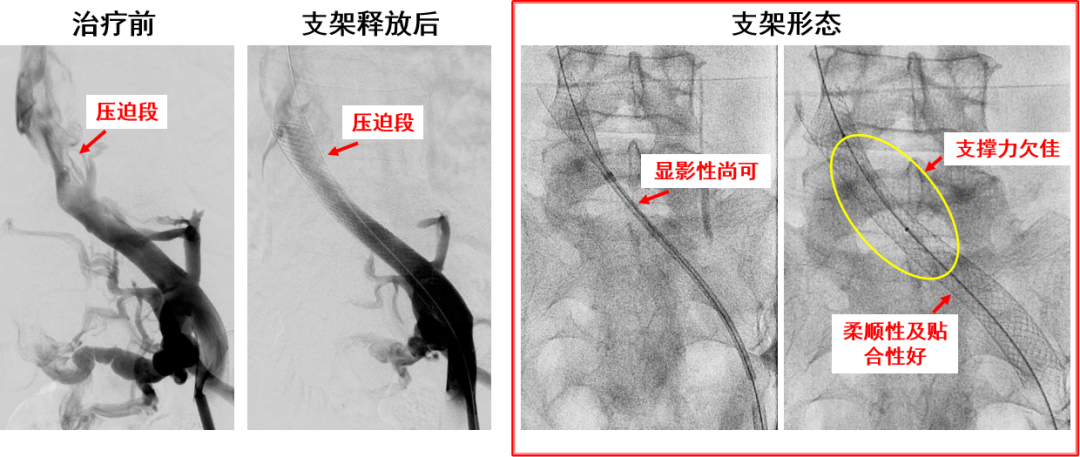

产品C:病例一(柔顺性及贴合性欠佳)

改进点:

开环部分支撑力欠佳

因锥形设计,远端尺寸小,支架选择困难,远端易出现支架“悬空”现象

近段闭环打开后无法回收